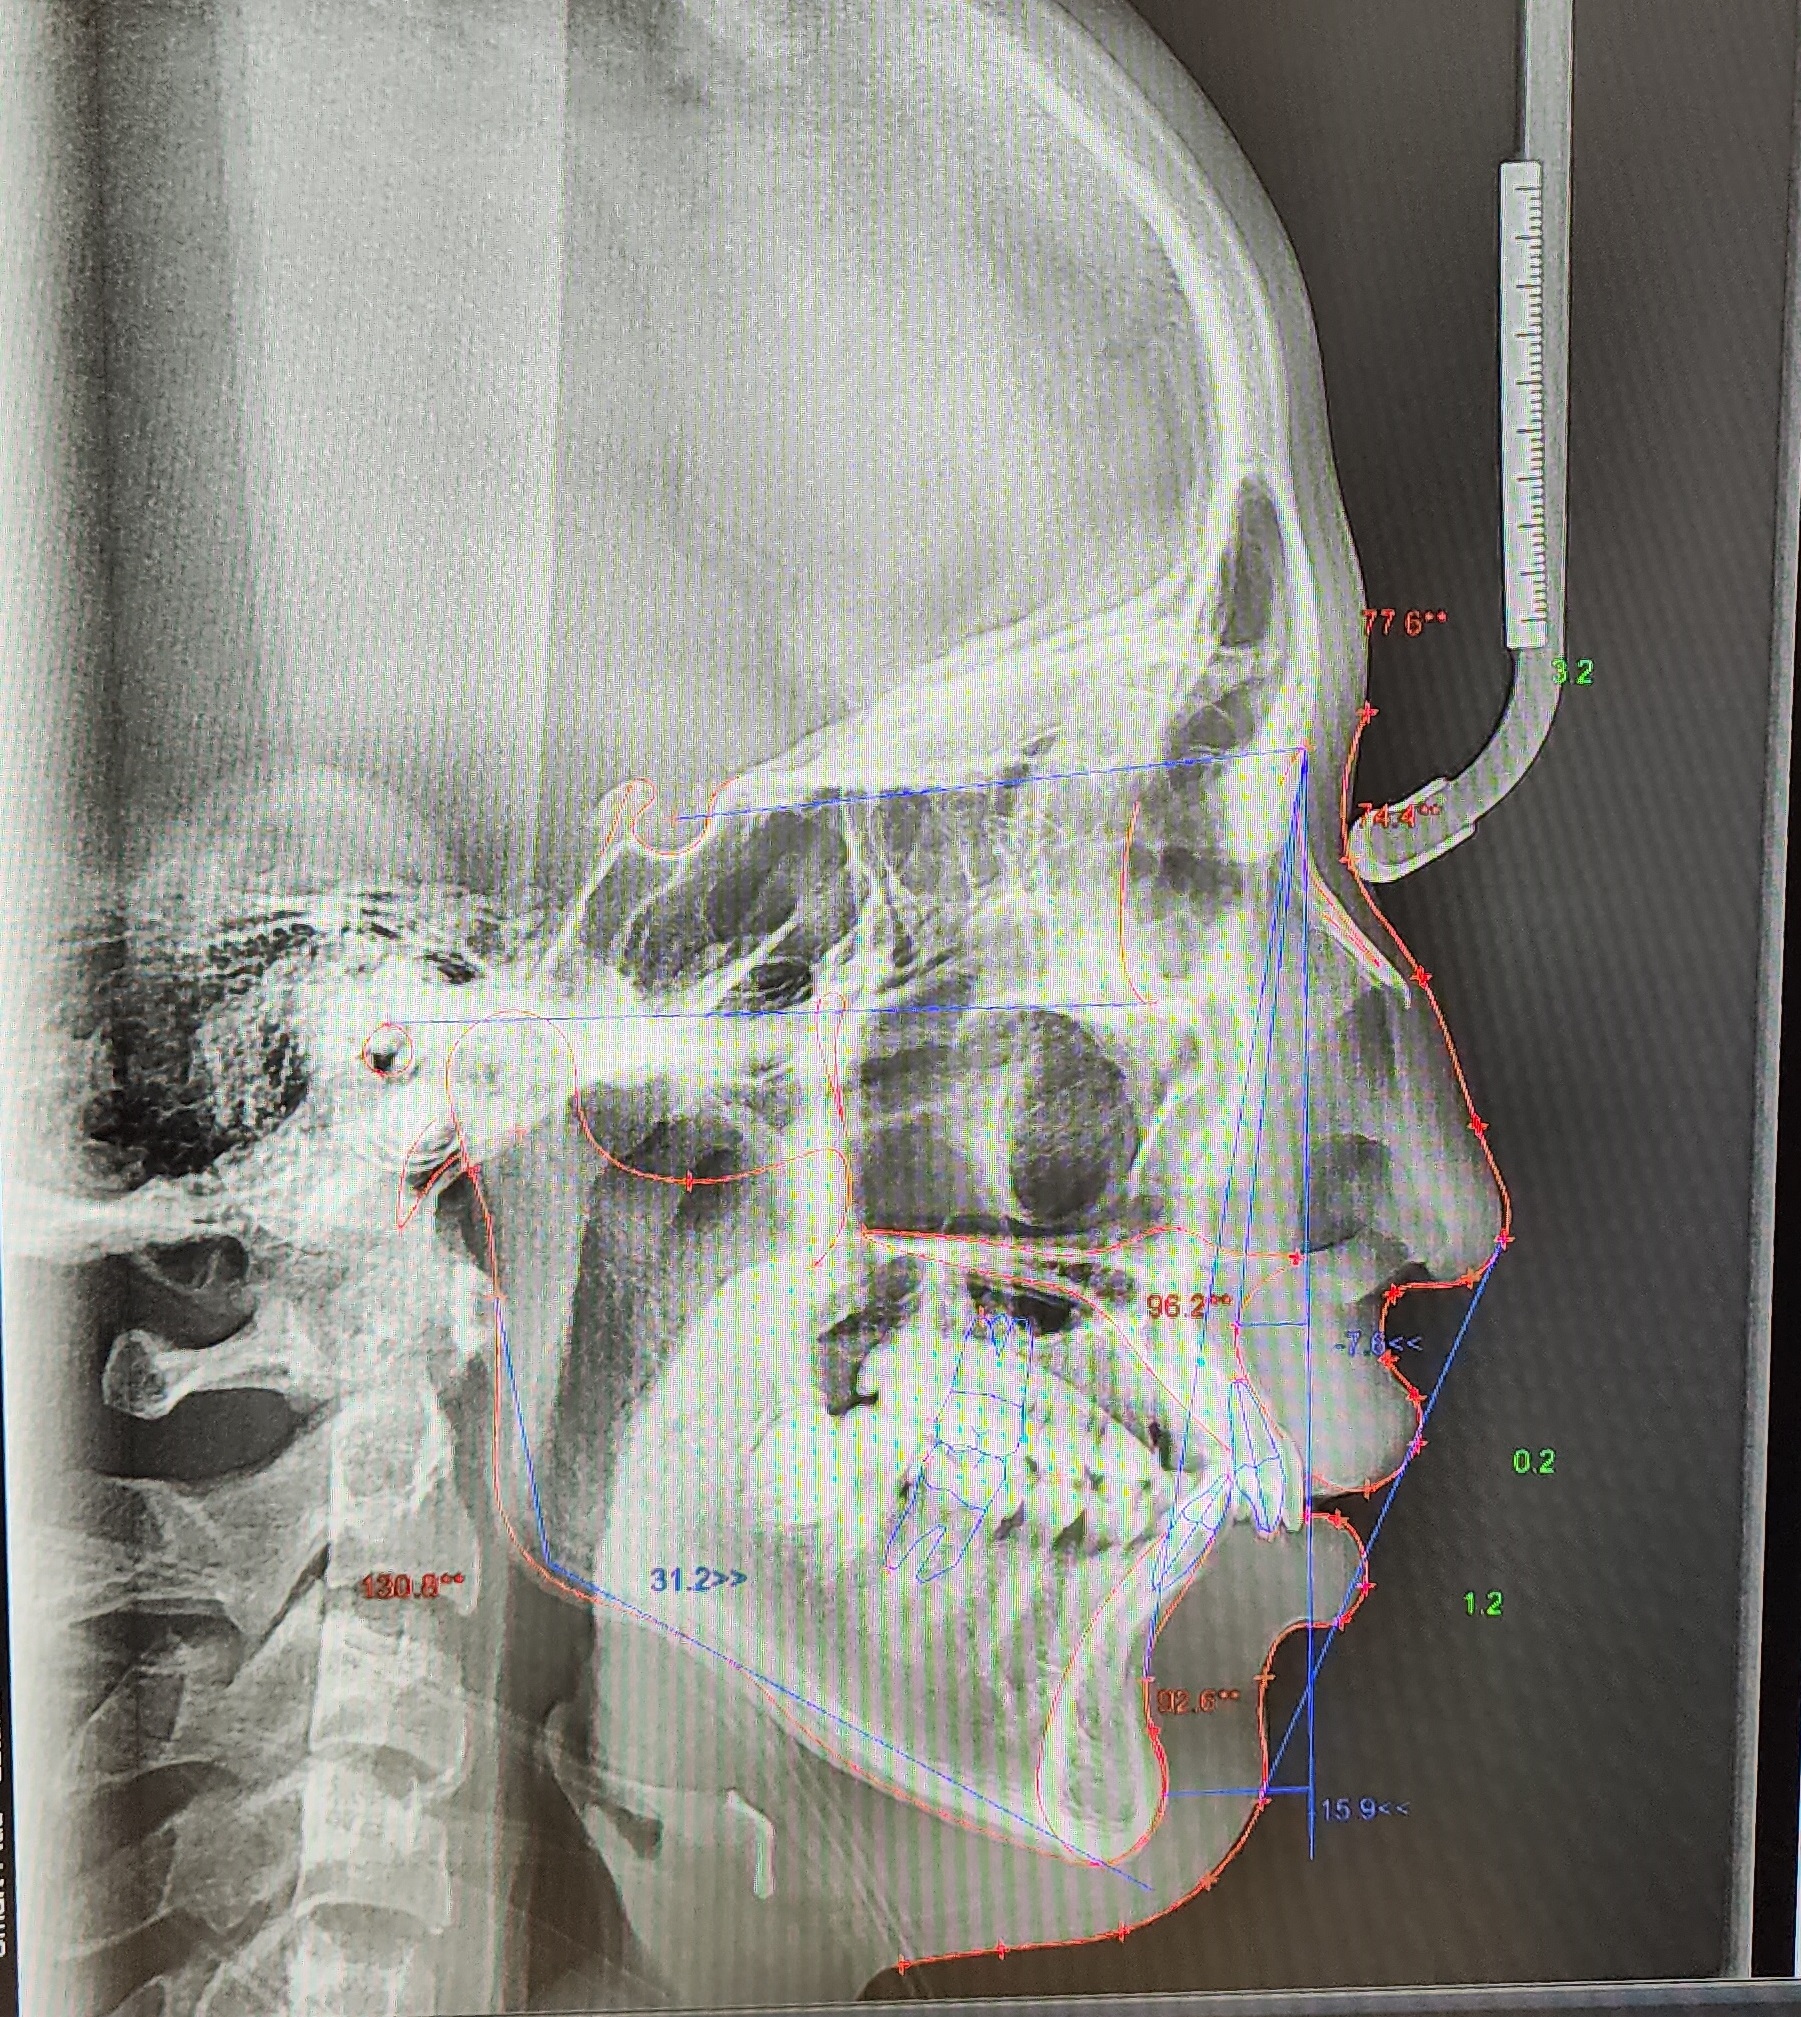

▼ 1차 정밀 검사 X-RAY

▼ 치아상태 및 얼굴 각도 치아 치수확인